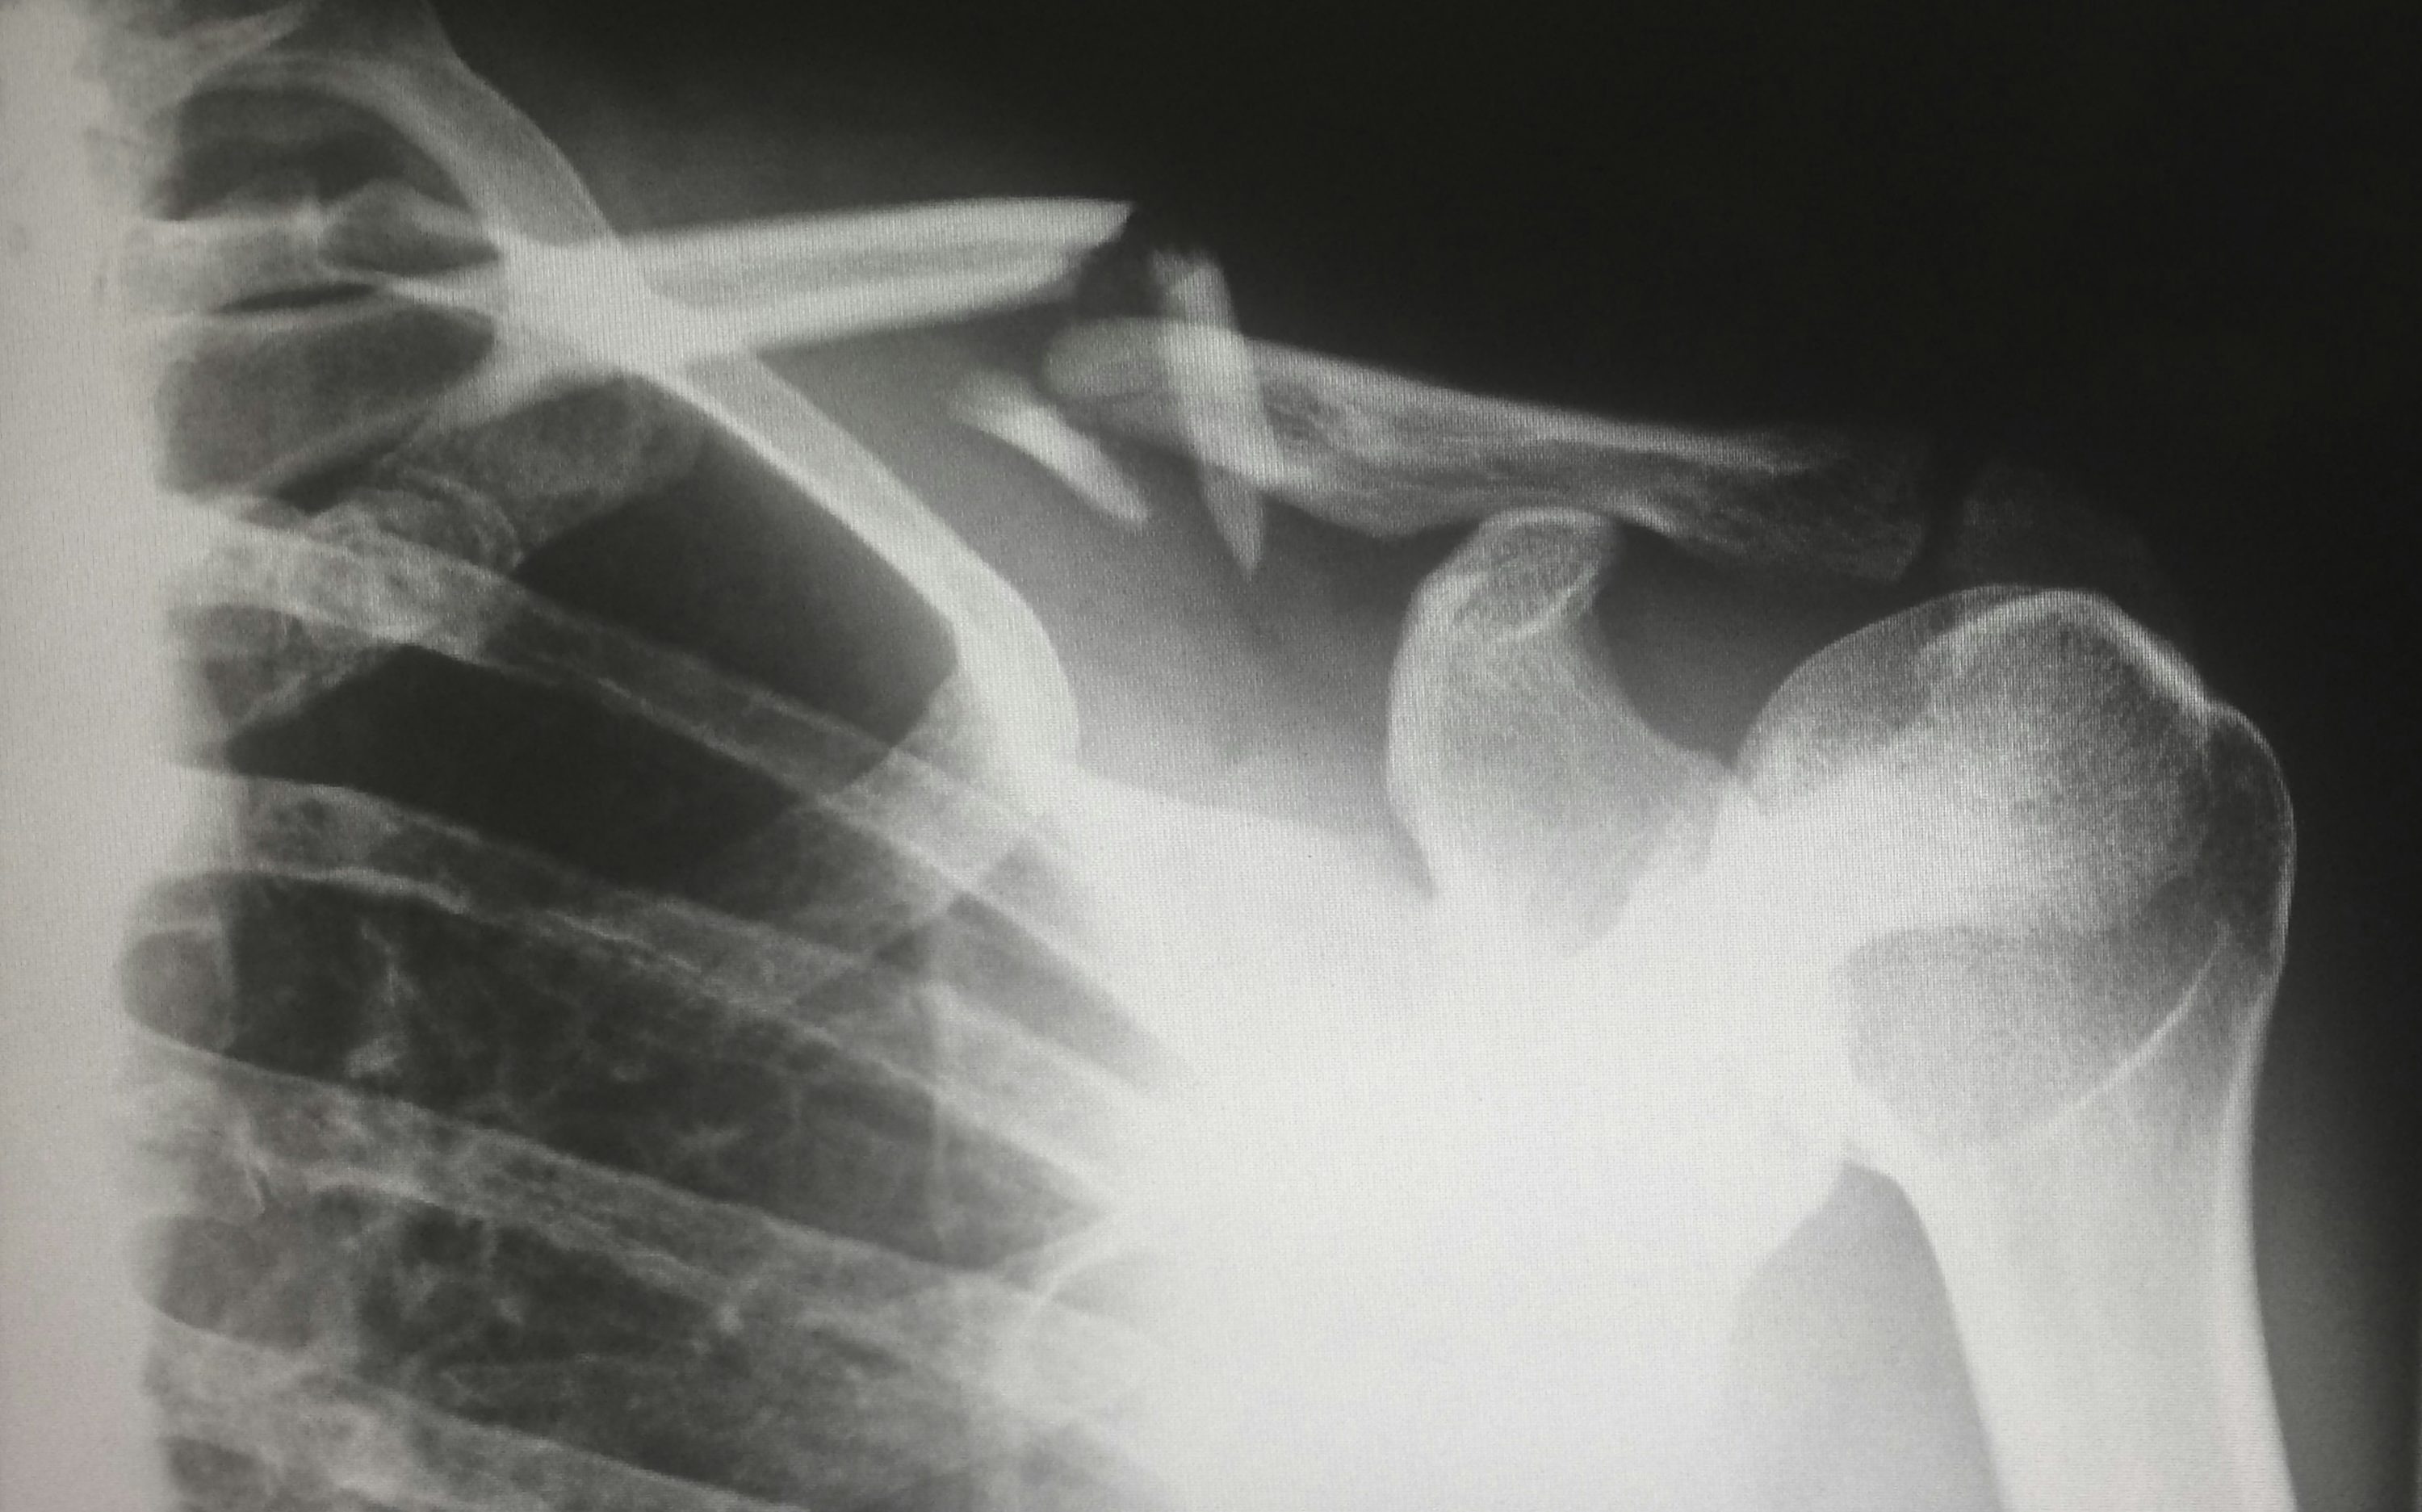

호흡이 조금만 힘들어져도 반드시 병원을 방문해 흉부 엑스레이나 CT 촬영 등을 받아보는 것이 중요합니다.

지인의 경우처럼 폐렴에서 유발된 흉수는 초기에 가벼운 기침과 미열로 시작했지만, 하루가 다르게 악화되었어요. 결국 병원에선 흉막에 1L 넘는 액체가 고여 있는 것을 확인했고, 즉시 흉수 배액 시술이 진행됐습니다.